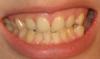

slavna Опубликовано 12 апреля, 2007 Поделиться Опубликовано 12 апреля, 2007 Прям сюда.Чем больше информации,тем лучше выкладываю фотографии, сканер пока не могу одолеть, если что завтра отсканирую на работе. Ссылка на комментарий

Премоляр Опубликовано 12 апреля, 2007 Поделиться Опубликовано 12 апреля, 2007 Вы сами себя фоткали?.Судя по фотографиям-лечение возможно с удалением,но никак не клыков(2х премоляров на н.ч.).Хотелось бы еще фотки в профиль и панорамный снимочек Ссылка на комментарий

slavna Опубликовано 12 апреля, 2007 Поделиться Опубликовано 12 апреля, 2007 Вы сами себя фоткали?.Судя по фотографиям-лечение возможно с удалением,но никак не клыков(2х премоляров на н.ч.).Хотелось бы еще фотки в профиль и панорамный снимочек сама фоткала, что совсем ужасно? я вот и сейчас пока выставляю фотки, прихожу в ужас, приходиться кривиться, раскрывать широко рот . Я не такая ужасная выкладываю еще то, что получилось. панарамный снимок прост сфотографировала, т.к. сканер не поддается мне предложили удалять четвертый слева, как раз который выпирает уже. А на верху у меня же больште щели, неужели нельзя сразу поставить или потом есть вариант после выравнивания низа "долепить" винирами ? извините за неграмотность в терминологии Ссылка на комментарий

Премоляр Опубликовано 12 апреля, 2007 Поделиться Опубликовано 12 апреля, 2007 Вот теперь и "щели" видно.Возможно,после ортодонтического лечения понадобится реставрация верхних премоляров для предания им формы клыков.(так естественнее)Если комплексуете-ставьте лингвальные брекеты.Клыки вам удалять НЕ БУДУТ.Успокойтесь. Ссылка на комментарий